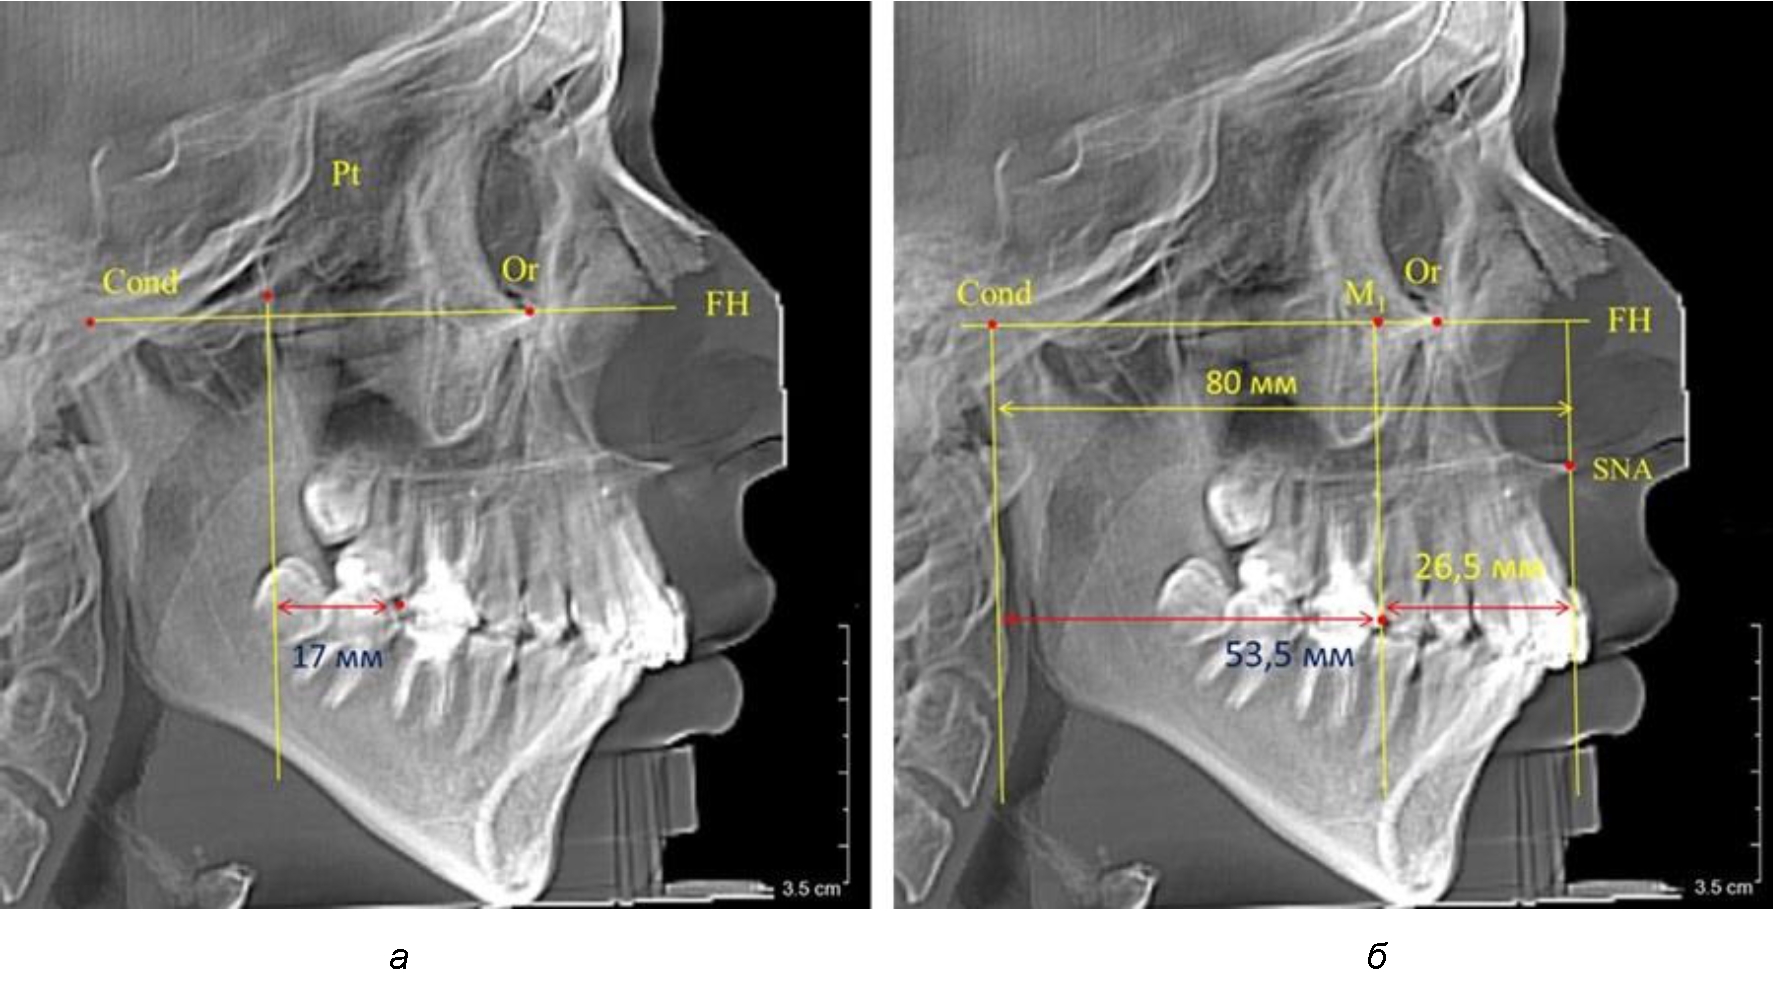

Рис. 2. Особенности положения первых моляров по R. E. McDonald (а) и по предложенному методу (б) при уменьшенном молярно-крыловидном расстоянии

Рис. 3. Особенности положения первых моляров по R. E. McDonald (а) и по предложенному методу (б) при увеличенном молярно-крыловидном расстоянии

Так, при расстоянии от крыловидной вертикальной плоскости PTV до дистальной поверхности верхнего первого постоянного моляра в 13 мм сагиттальный размер гнатического отдела был 82 мм. При этом отношение кондилярно-спинального расстояния к кондилярно-молярному размеру (54,5) было близким к коэффициенту 1,5, что представлено на рис. 2.

В то же время при увеличенном расстоянии от крыловидной вертикальной плоскости PTV до дистальной поверхности верхнего первого постоянного моляра, равное 23 мм, сагиттальный размер гнатического отдела составил 92 мм. При этом отношение кондилярно-спинального расстояния к кондилярно-молярному размеру (30,5), так же, как и при малых размерах, было близким к коэффициенту 1,5, что представлено на рис. 3.